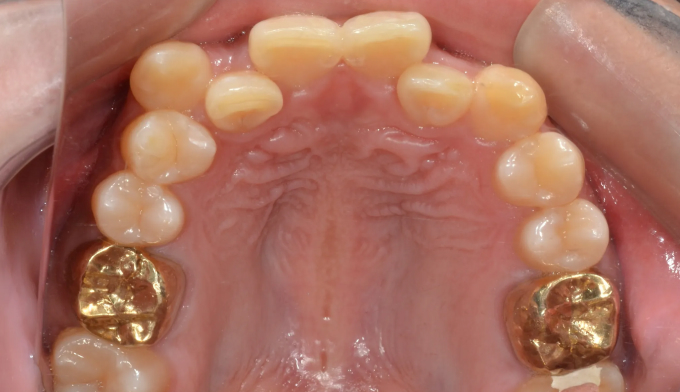

덧니

필요한 공간이 많지 않아도, 입이 많이 나오지 않아도 발치교정을 해야하는 경우들이 종종 있습니다.

비발치교정시 주로 악궁확장이나 치아삭제, 또는 치아 후방이동을 통해 공간을 확보하는데 기존의 악궁이 충분히 넓거나 치아크기가 작은경우, 또는 사랑니가 너무 깊숙히 있어서 발치하기 어려운 경우에는 어쩔 수 없이 작은어금니 발치를 통해 공간을 확보합니다.

교정기간은 총 22개월입니다.